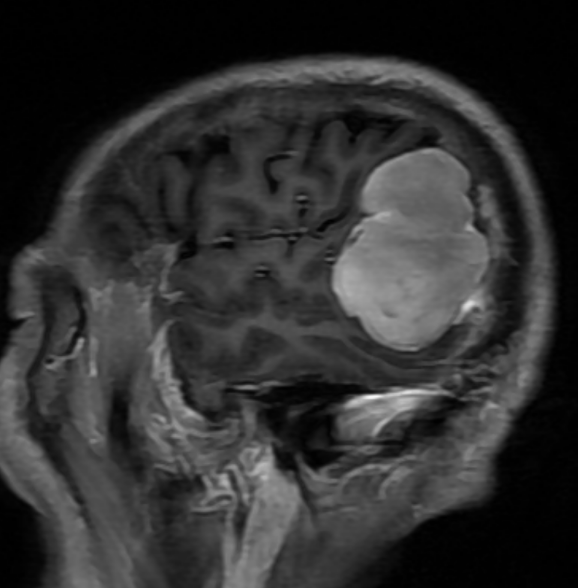

69岁的王大爷,因头痛在外院查出右颞顶区5厘米肿瘤,同时伴有严重肺部感染。转入岳阳市人民医院后,经过一周积极治疗,待其肺部情况稳定,神经外科团队立即接手。

尽管肿瘤质地坚韧,与周围血管粘连紧密,但团队凭借过硬的显微技术功底,仅用2小时便干净利落地完成了肿瘤切除。整个手术过程精准、流畅,充分展现了团队应对不同位置、不同难度颅内病变的丰富经验和高效协作能力。